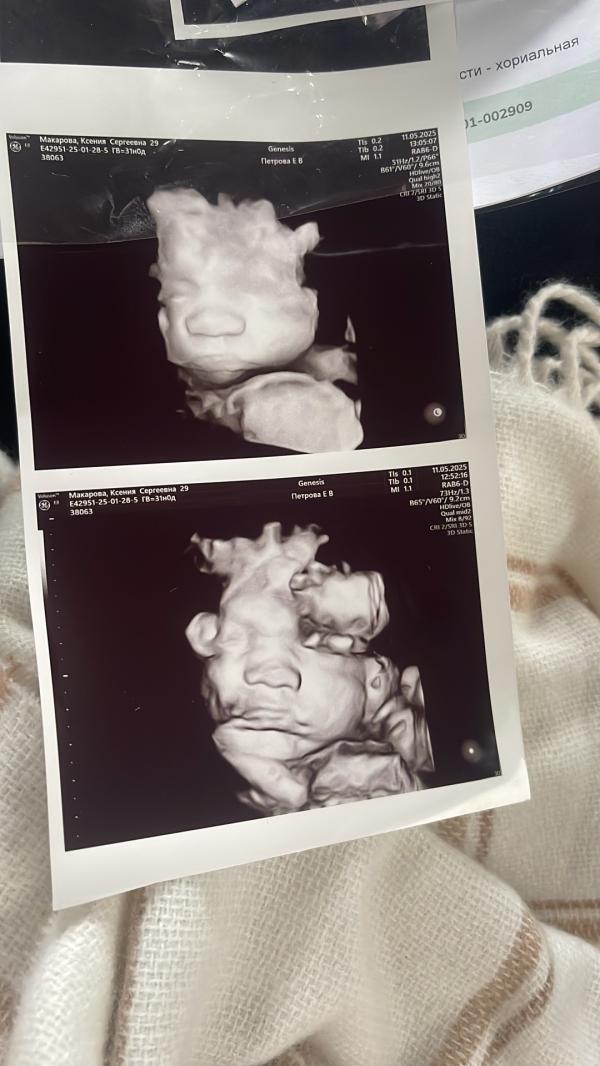

Были сегодня на третьем узи

Такая сладкая булочка уже 🥰

Вес +-2063 кг, ровно 31 неделя

Какой носик-кнопочка 😍